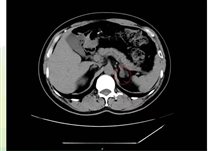

肾上腺CT正常表现

1.形态:形态各异;右侧:斜线状、倒“V”、倒“Y”形;左侧: 倒“V”、倒“Y”形或三角形;三维重建呈叶状。

2.大小: 侧支厚度<10mm;侧支厚小于同侧膈肌脚,面积小于150mm。

3.密度: 均匀,边缘光滑,无外凸结节。

4.强化: 均匀,边缘光滑。

肾上腺腺瘤CT表现

1.肾上腺腺瘤发生于肾上腺皮质,含脂质;

2.直径多小于3cm;

3.CT值<10HU;

4.出血、坏死、囊变少见;5.CT增强:早期快速廓清